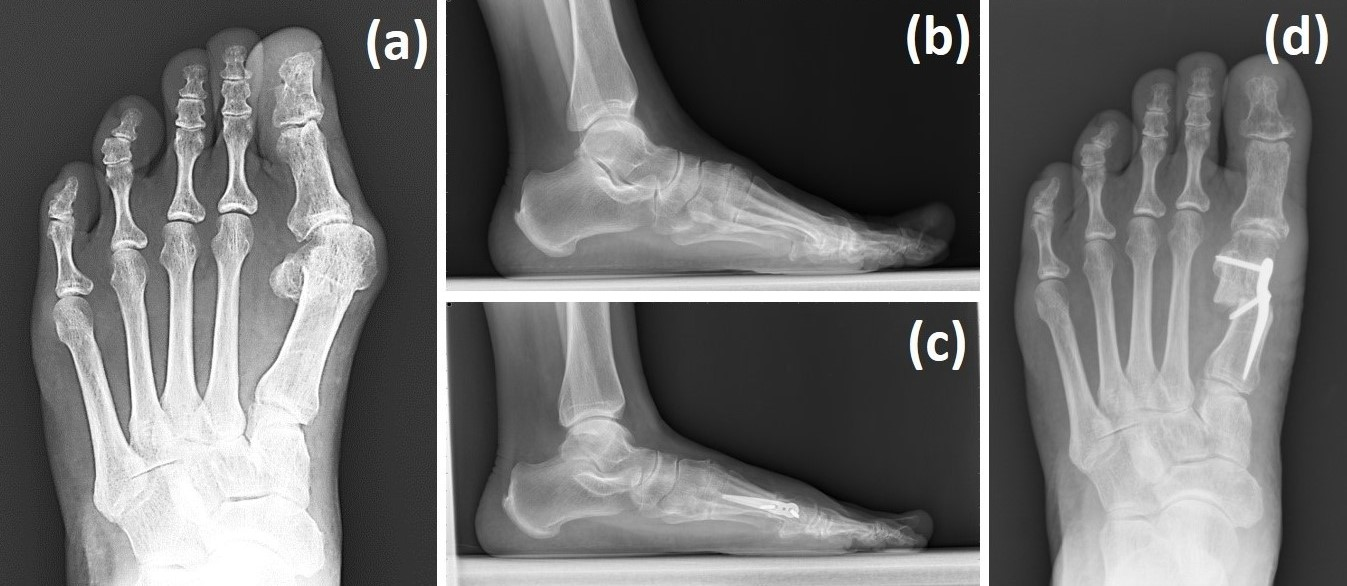

At our institution, the senior surgeon employs a targeted step-wise algorithm incorporating the Spear plate (Aplus Biotechnology Company, New Taipei City, Taiwan), Wilson osteotomy, and/or distal soft tissue balancing depending on preoperative findings (Figure 1).

In particular, patients with sesamoid non-reduction or a DMAA ≥ 15° and without tarsometatarsal (TMT) joint hypermobility or degenerative changes undergo a Wilson osteotomy with correction in both the transverse and frontal planes, combined with distal soft tissue release and Spear plate fixation.

Figure 1. HV revision surgery performed using the Spear plate with Wilson osteotomy combined with a distal soft tissue procedure. The left foot of a 63-year-old male patient with HV recurrence was corrected, as shown in the above weight-bearing radiographs. (a,b) Preoperative radiographs and (c,d) 3-month-postoperative radiographs.